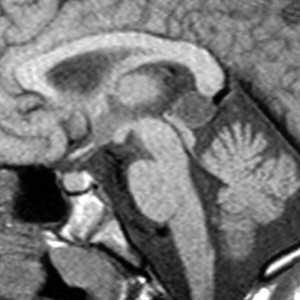

Дольчатые образования, которые заполняют, расширяют ликворные пространства, оказывают постепенно нарастающий масс-эффект, проникают между структурами и охватывают соседние нервы и сосуды. Частой особенностью кист задней черепной ямки является смещение основной артерии в сторону от моста.

Сочетание клеточных остатков вместе с высоким содержанием холестерина понижают плотность эпидермоидов приблизительно до 0 HU; таким образом, эпидермоидные кисты могут быть идентичными по плотности с ликвором, и выглядеть так же, как арахноидальные кисты.

Кальцификация не часто (10-25% случаев); редко эпидермоидная киста может быть гиперденсной вследствие кровотечения, омыления или высокого содержания белка ("белые эпидермоиды").

Они не копят контраст, и только в очень редких случаях демонстрируют накопление контраста стенкой.

Могут вызывать эрозию костей, а при интрадиплоическом расположении имеют выраженный склеротический ободок по краям кисты [2].